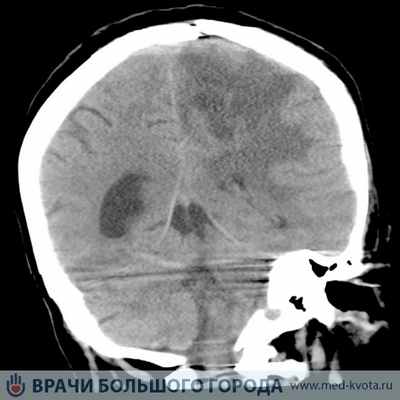

Не инвазивная диагностика глиальных опухолей

Для установления диагноза глиальная опухоль используется сочетание клинических данных (анамнез, неврологический и нейроофтальмологический осмотр), и результатов нейровизуализационных исследований: спиральная компьютерная томография (СКТ), магнито-резонансная томография (МРТ), МР и КТ – перфузия, а так же радионуклидных методов диагностики: однофотонная эмиссионная компьютерная томография (ОФЭКТ 99сTc – технеций) и позитронно-эмиссионная к компьютерная томография с мечеными аминокислотами (11С -метионин).

Когда возникает подозрение на онкоочаг в головном мозге, какие обследования надо пройти, чтобы проверить его? Выявить глиому ствола головного мозга, определить ее месторасположение, размер можно по фото и снимкам инструментальных исследований.

- • фотографии КТ, МРТ. ПЭТ-КТ, которые проявляют особенности образования;

Наиболее приемлемым способом диагностики глиомы головного мозга на сегодняшний день является МРТ головного мозга. При невозможности ее проведения может применяться МСКТ или КТ головного мозга, контрастная ангиография мозговых сосудов, сцинтиграфия.